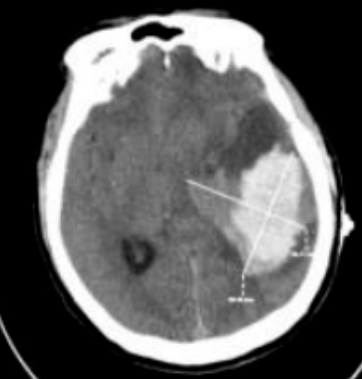

一名中年男性因突发意识障碍紧急入院,头颅CT提示颞叶大量脑出血。长春国文医院神经外科团队迅速启动绿色通道,在充分评估并与家属沟通后,急诊实施神经内镜下脑内血肿清除术。

神经内镜技术为脑出血治疗提供了新的手术方式。手术采用小骨窗入路,内镜自带高清冷光源与摄像头,可清晰呈现血肿腔深部结构,帮助术者分辨血肿、脑组织及重要血管神经;

在内镜直视下,医生可多角度清除凝固血块,其清除效率高于传统穿刺引流;高清放大的视野有助于发现活动性出血点并进行电凝处理。由于手术入路对正常组织的干扰较小,患者术后生理状态更为平稳,住院周期相应缩短。